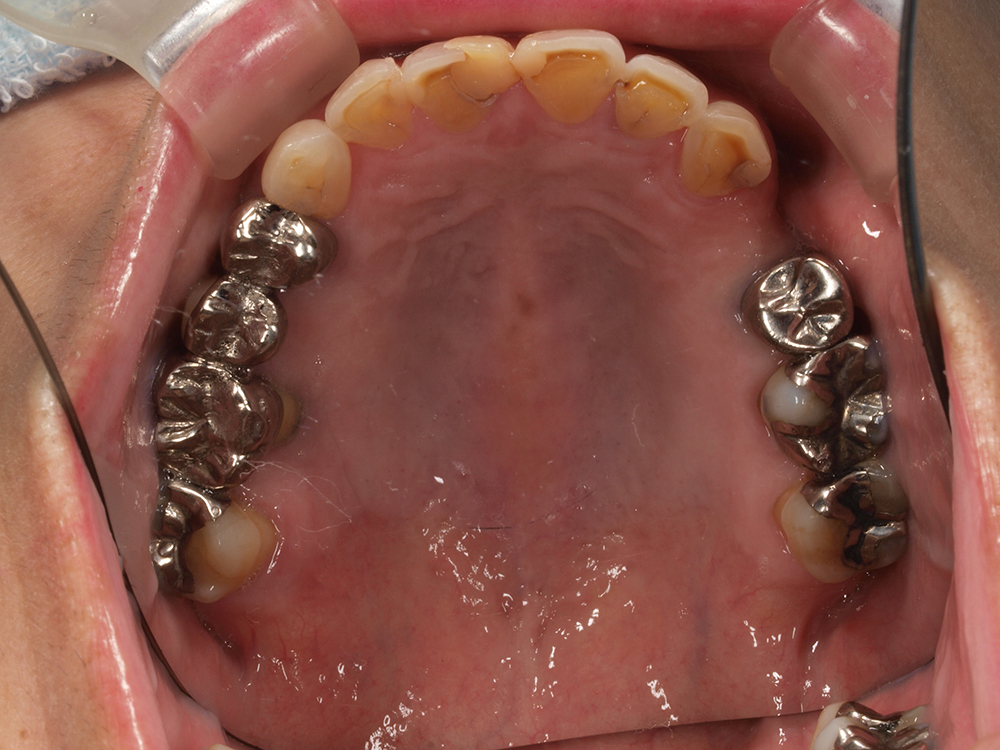

64歳 女性 紹介患者様

- 主訴

- 上下左右の歯が無くて、食べずらい、右下の歯が痛い

- 処置内容

- 右上3本、左上1本、右下3本、左下3本、鎮静麻酔

- 治療費用

- 上顎:約180万円(税込)下顎:約170万円(税込)

- 治療期間

- 上顎:約9か月、下顎:約6か月

- リスク

-

術後の腫れ、痛み(ピークは3日後、1週間で軽減)

上部構造物、仮歯の破折、人工歯根脱落リスクがあります